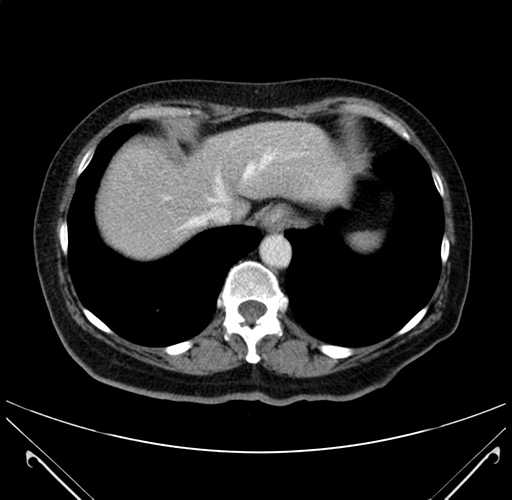

Pre-Chemo: Axial Venous

Axial Venous